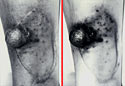

Click for larger image and description

Figure 70. Melanin in malignant melanoma.

Figure 71. Same, three months later.